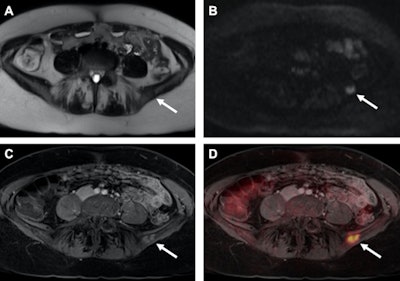

With the relatively recent advent of PET/MRI, the "successful integration of the PET component within an MR-scanner provides a new generation of multimodal imaging, combining functional PET data with structural and functional information of MRI," the authors wrote.

In addition, the scans revealed a total of 165 suspect lesions, of which there were 122 malignant tumors (74%) and and 43 benign lesions (26%). Among the 25 patients with breast cancer relapse, 18 patients (72%) experienced metastatic disease. The other seven patients (28%) suffered from unifocal cancer localizations, and a local breast cancer recurrence was found in five patients (20%).

Regarding lesion conspicuity and differentiating between malignant and benign lesions, contrast-enhanced T1-weighted VIBE imaging performed the best with significantly higher values compared with T2-weighted HASTE or DWI. T2-weighted HASTE also outperformed DWI in distinguishing benign lesions, while there was no statistically significant difference between the two MR sequences in differentiating malignant lesions (p > 0.05).